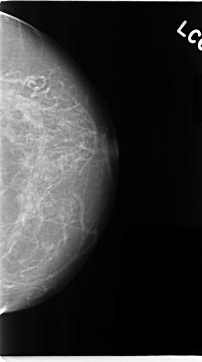

C_0067_1.LEFT_CC

LEFT_CC LINES 4704 PIXELS_PER_LINE 2616 BITS_PER_PIXEL 12 RESOLUTION 50 NON_OVERLAY